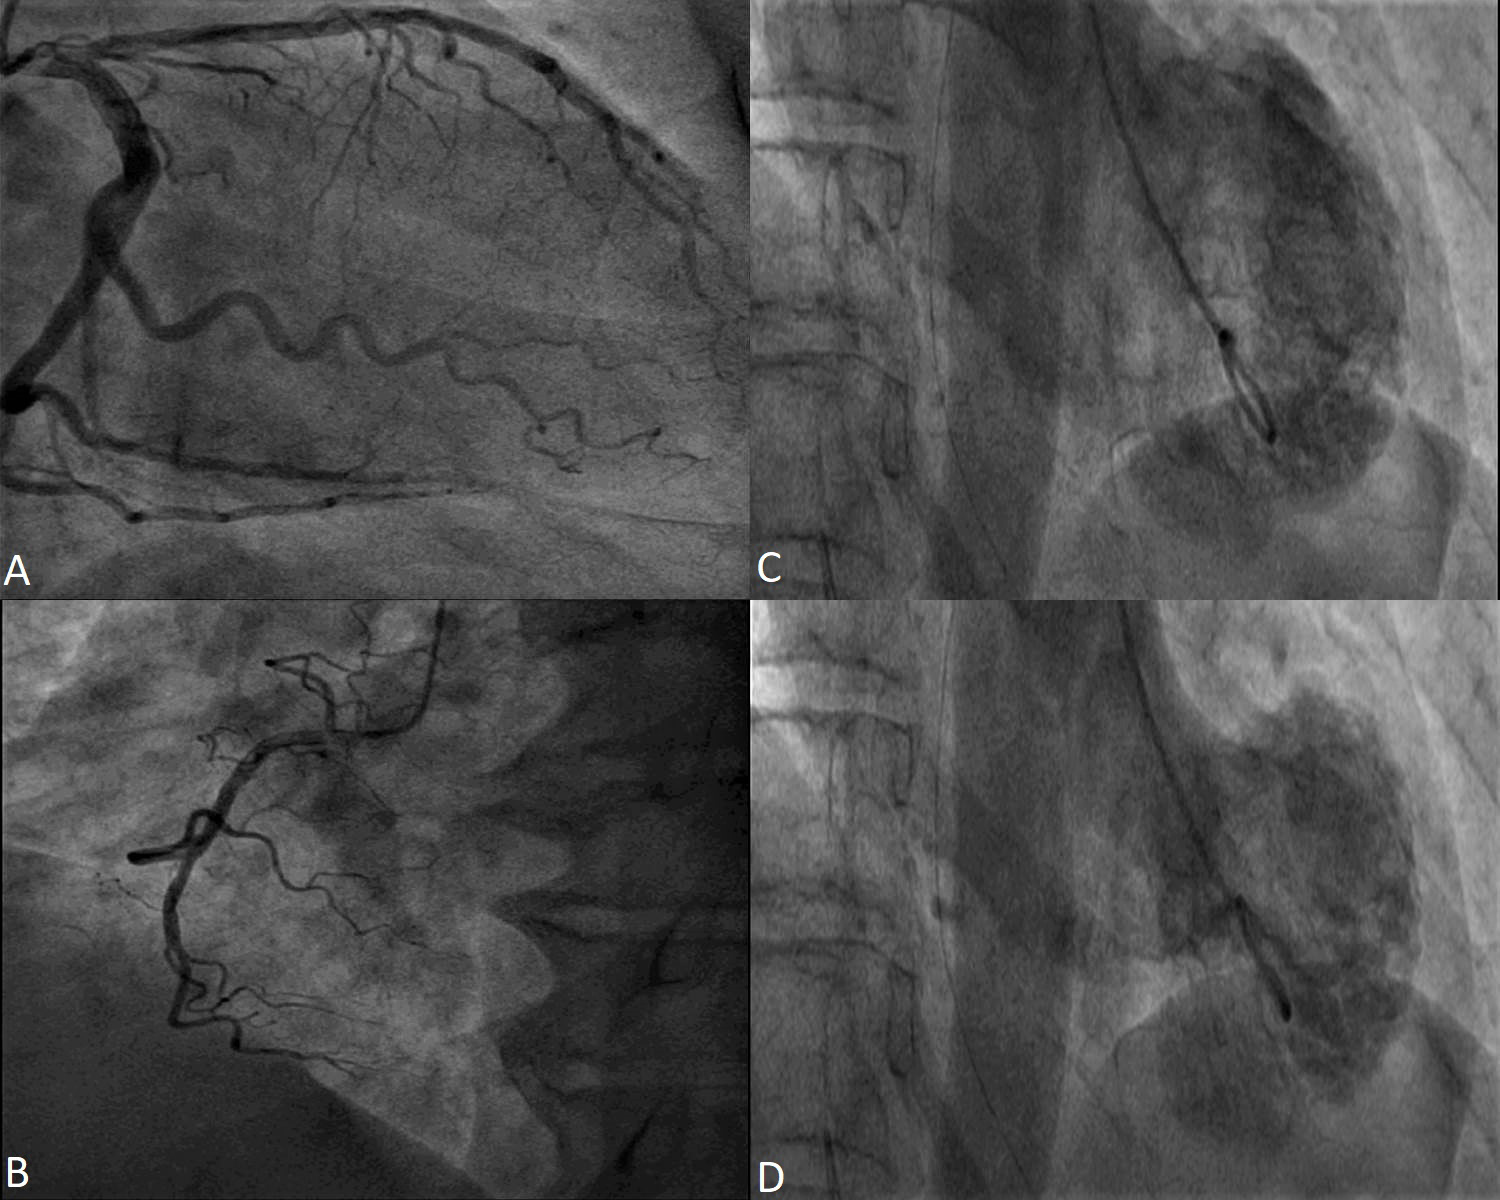

It is mainly used in documenting LV systolic and diastolic function [45]. The RWMA is usually of a circumferential pattern and extend beyond the distribution of one coronary artery. The most frequent phenotype is the apical pattern — akinesia of the apical segments of the LV with basal compensatory hyperkinesis (Fig. 2). Atypical patterns are those affecting medioventricular, basal or focal myocardial territory [46, 47, 48, 49]. Case reports have described isolated right ventricular (RV) Takotsubo [50, 51].

Fig. 2.Transthoracic echocardiography images apical four-chambers views of a 73 year-old female patient with Takotsubo Syndrome. Apical akinesia in the acute phase (A and B) and normalized wall motion and ejection fraction at 1 month follow-up (C and D).

But the role of ultrasound imaging does not end here. Through its definition, TS

is a reversible systolic dysfunction, thus extending the role of echocardiography

from diagnosis to follow-up [76, 77] [Fig. 2]. It is necessary to document the

recovery of the ventricular systolic function –and the progression or regression

of complications [54, 78]. As diagnostic Takotsubo Criteria mention, the wall

motion anomalies are transient [2, 4, 5]. As a result, echocardiographic follow-up

is mandatory, especially if the patients cannot be evaluated by CMR. As

demonstrated in this thorough study, the LV systolic function improves in the

first 2 weeks and continues to recover over the next 4 weeks [79]. Documenting

the left ventricular ejection fraction (LVEF) also has prognostic implications. Reduced ejection fraction